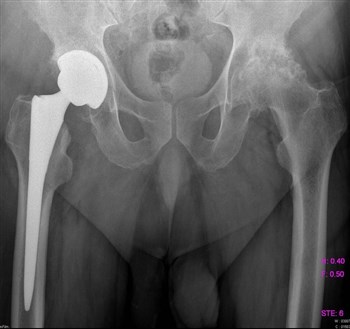

Артроз тазобедренного сустава

Для того, чтобы поставить верный диагноз, проводят диагностику, которая включает:

- МРТ;

- Рентгенографию;

- Компьютерную томографию.

Проведенная диагностика покажет, в какой стадии находится заболевание, будет дана точная информация о состоянии мягких и костных тканей.

Если заболевание не в хронической форме, или, проще говоря, не запущено, то лечение происходит обычным парацетамолом, без какого-либо хирургического вмешательства. Лечащий доктор назначает курс массажа, лечебной гимнастики, постоянный контроль ортопеда. При ноющих болях прописывается курс болеутоляющих – Кеторол, Диклофенак.